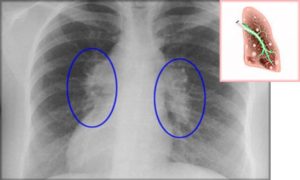

Характерные изменения при саркоидозе выявляются при рентгенографии легких, в ходе КТ или МРТ легких — определяется опухолевидное увеличение лимфоузлов, преимущественно в корне, симптом «кулис» (наложение теней лимфоузлов друг на друга); очаговая диссеминация; фиброз, эмфизема, цирроз легочной ткани. У более половины пациентов с саркаидозом определяется положительная реакция Квейма – появление багрово-красного узелка после внутрикожного введения 0,1—0,2 мл специфического саркоидного антигена (субстрата саркоидной ткани больного).

- Рентгенография и КТ — определяется симптом «матового стекла», синдром легочной диссеминации, фиброз, уплотнение легочной ткани;

- рентгеноскопия и рентгенография органов грудной клетки – позволяют обнаружить мельчайшие изменения в дыхательной системе уже на начальных этапах заболевания;

Функциональные нарушения в легких можно оценить в результате проведения рентгенографии

В случае, если у человека обнаружен саркоидоз легких, прогноз для жизни зависит от степени тяжести заболевания и обширности изменений в дыхательной системе. Функциональные нарушения в легких можно оценить в результате проведения рентгенографии.

Первая стадия – сопровождается увеличением размеров внутригрудных лимфатических узлов, изменения в анатомическом строении легкого не наблюдаются.

Вторая стадия – продолжается процесс роста лимфатических узлов, на поверхности легких можно рассмотреть темные пятна и узелки различных размеров, происходят изменения нормального строения в средних и нижних отделах легкого.

Третья стадия – легкое прорастает соединительной тканью, гранулемы начинают увеличиваться в размерах и сливаться между собой, плевра заметно утолщается.

Четвертая стадия – сопровождается глобальным разрастанием соединительной ткани, нарушениями нормального функционирования легких и других органов дыхательной системы.